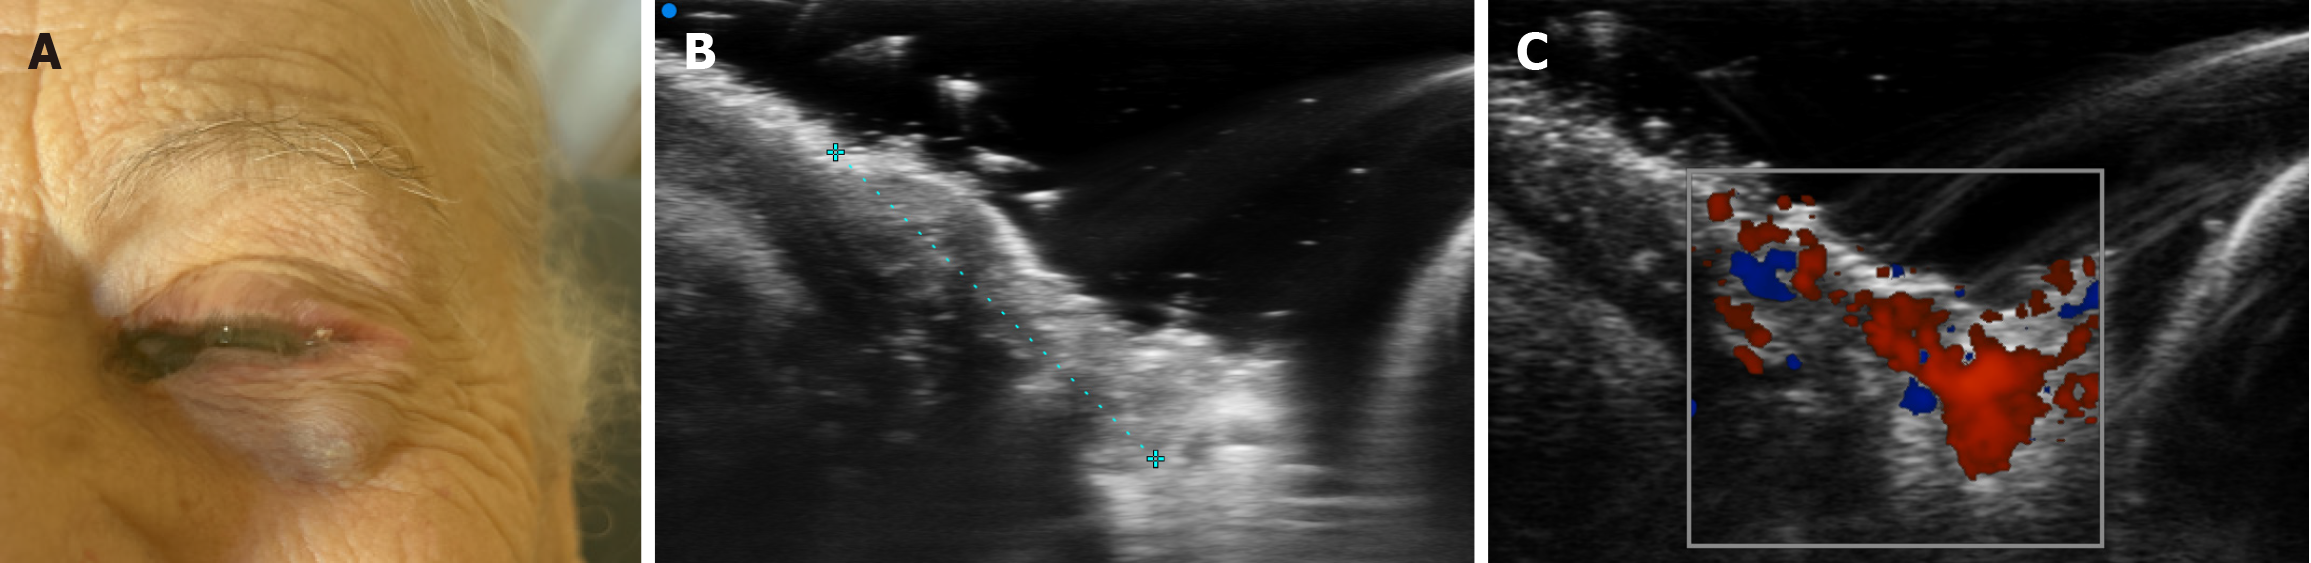

Figure 4 Multimodal evaluation of a subepidermal nodule in the lower eyelid, suspicious for conjunctival satellite metastasis.

A: Real-time clinical photograph with arrow indicating the anatomical location of the palpable lesion along the left lower eyelid; B: Ultra-high-frequency ultrasound image (48 MHz) showing a well-demarcated, hypoechoic subepidermal nodule (9 mm × 8 mm) with scattered hyperechoic foci; C: Color Doppler image revealing increased and accelerated perilesional vascularization, consistent with active neoplastic tissue.